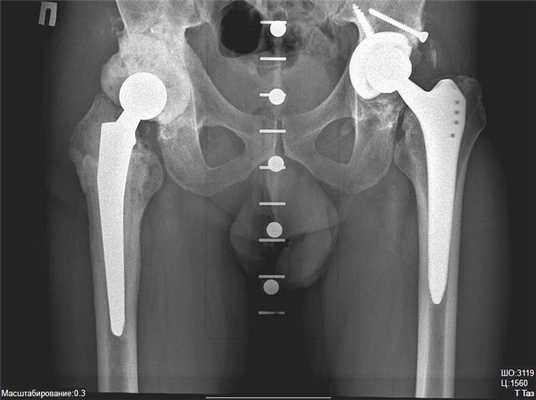

Интересный случай, двухсторонняя замена ТБС, но по разным технологиям. Слева тотальное протезирование, справа поверхностное.

Одновременное двустороннее эндопротезирование ТБС, рекомендуется в исключительно редких ситуациях, операционная травма будет больше, а, следовательно, и риск осложнений возрастет.